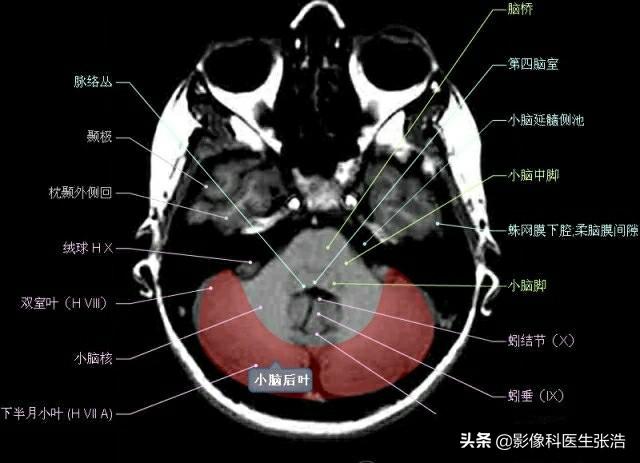

核磁共振(MRI)是一種利用磁場(chǎng)和射頻脈沖來(lái)生成身體內部結構的詳細圖像的非侵入性檢查技術(shù),頭部核磁共振主要用于檢查腦部疾病、神經(jīng)系統問(wèn)題以及血管狀況等,這項檢查對于疾病的早期發(fā)現和治療具有非常重要的意義。